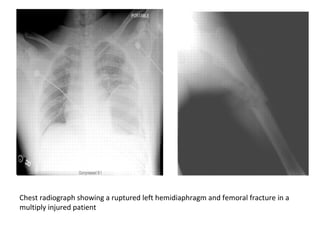

Chest radiograph showing a ruptured left hemidiaphragm and femoral fracture in a

multiply injured patient

Initial external fixation was performed at the time of the diaphragmatic repair

Chest radiograph showinga ruptured left hemidiaphragm and femoral fracture in a multiply injured patient

Initial external fixationwas performed at the time of the diaphragmatic repair